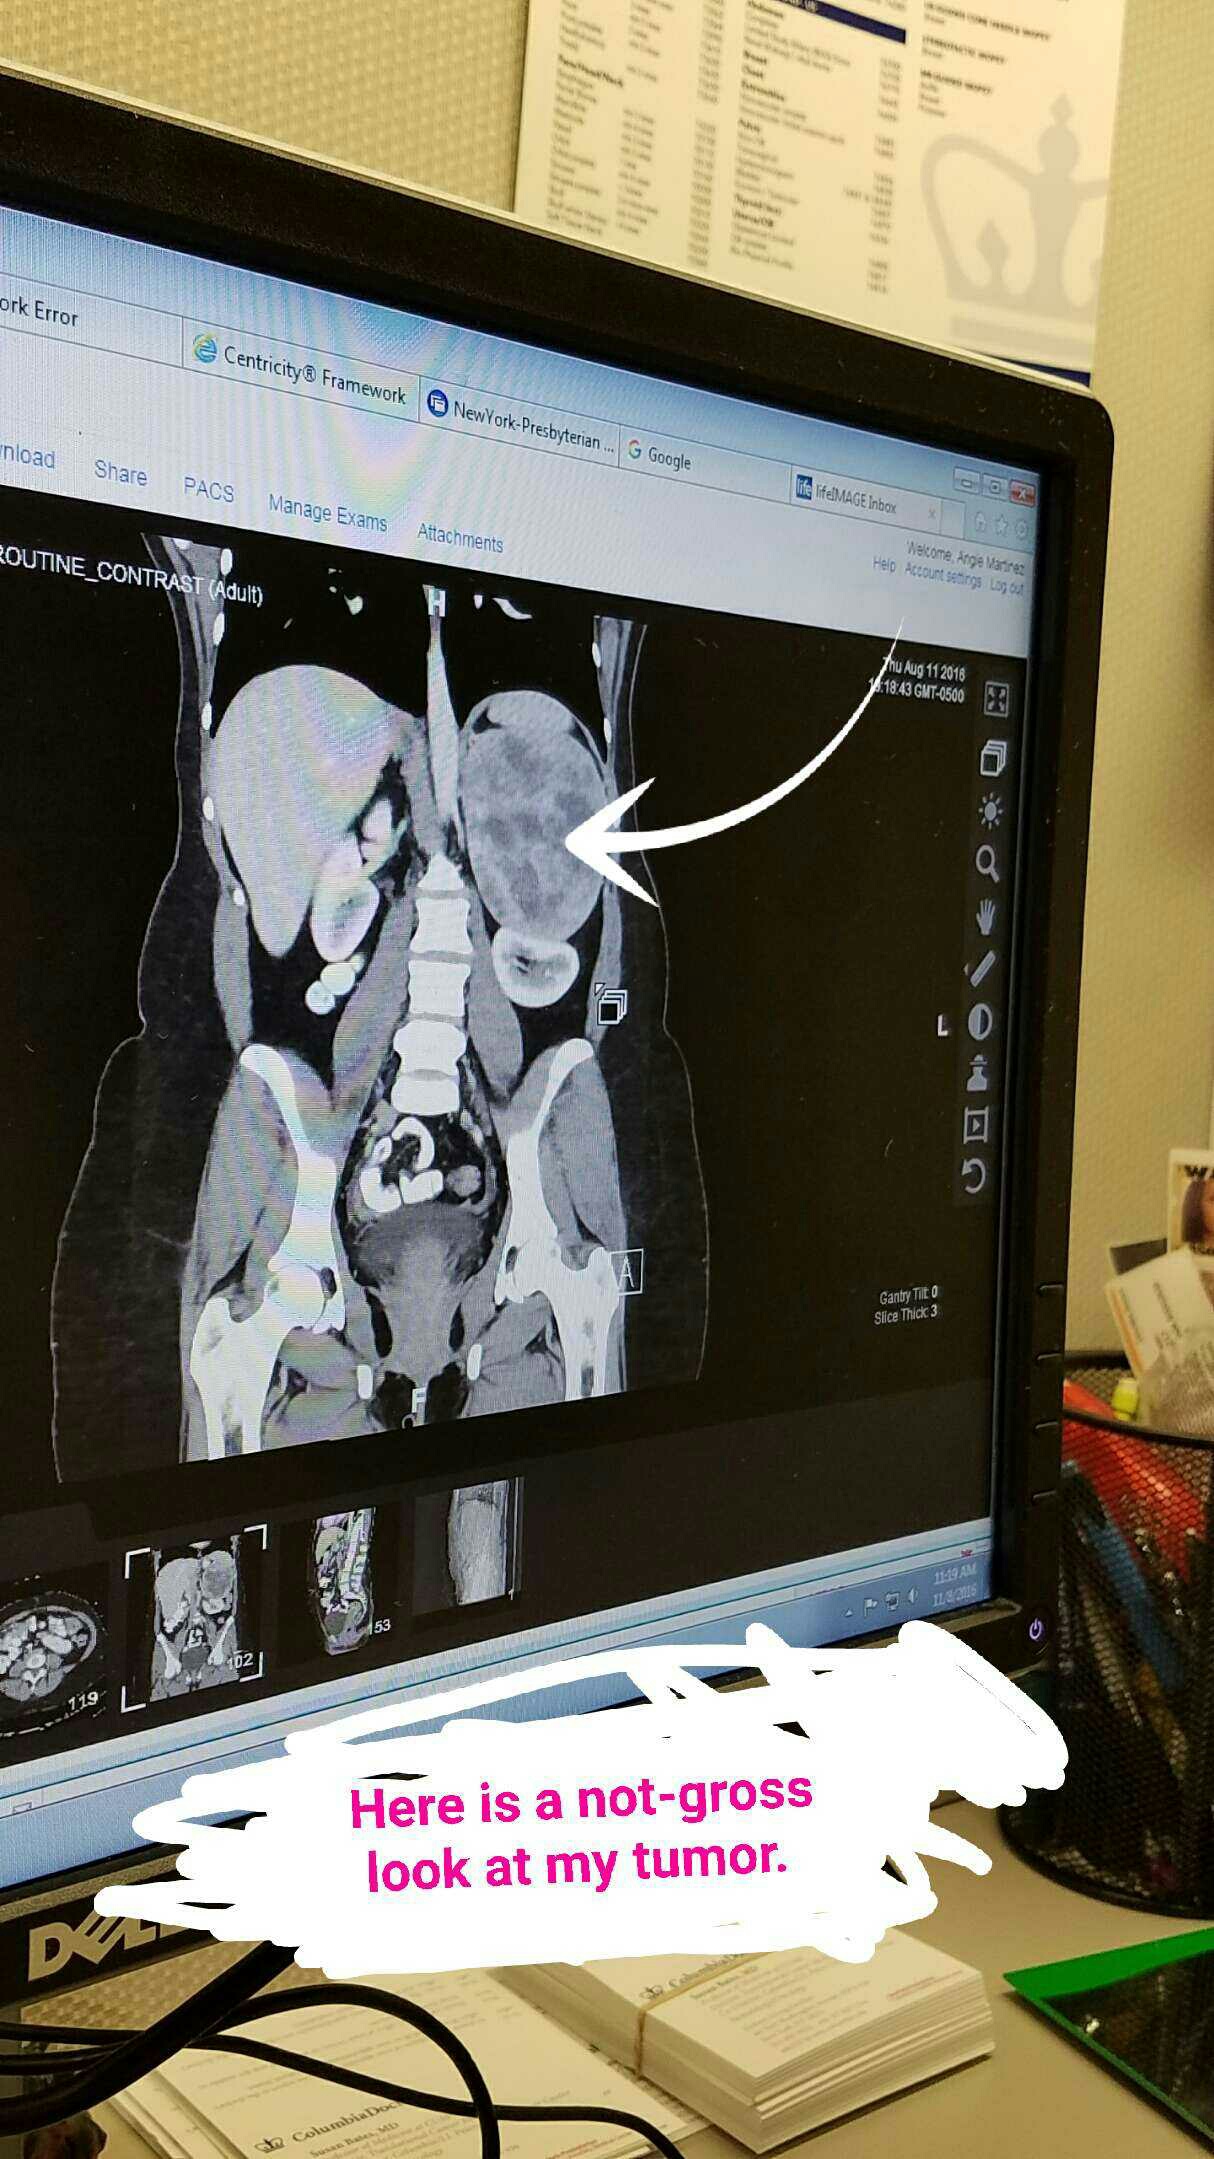

My first appointment with lasted nearly an hour during which time he examined both me and my records thoroughly, introduced me to the Weiss system for analyzing the malignancy potential of tumors like mine, showed me my CT scan images and hugged me – twice.

That splotchy thing? My giant tumor.That splotchy thing? My giant tumor.

That splotchy thing? My giant tumor.